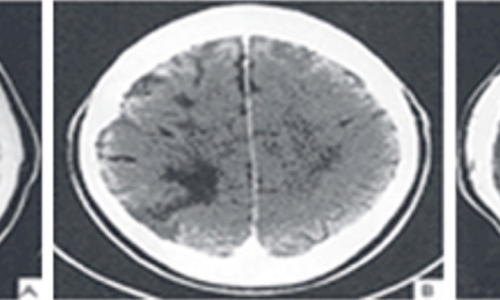

뇌졸중에서도 혈관이 막히는 뇌경색이야말로 촌각을 다투는 응급질환이라고 볼 수 있습니다. 뇌혈관이 막히면서 점차 뇌세포가 괴사하기 때문에, 증상 발현 3시간 안에 혈전용해제를 투여하고 시술에 들어가야 심각한 상황을 면할 수 있습니다. 뇌경색 치료방법에 있어 가장 중요한 것은 혈전을 녹이는 혈전용해제를 정맥 투여함으로써 막힌 혈관을 뚫어주는 것입니다. 하지만 혈전용해제의 경우도 출혈 가능성이 있는 환자에게는 투여할 수 없으며, 또한 혈소판 수치가 낮아서 지혈이 되지 않는 경우에는 제외된다고 합니다.

또한 과거에 이미 뇌출혈이 발생한 경우와 고혈압 환자의 경우도 혈전용해제를 투여할 수 없다으며 보통은 약50% 정도의 환자에게만 혈전 용해제를 이용한 치료가 가능합니다. 막힌 혈관을 뚫어주는 치료를 한 이후에도 뇌경색은 꾸준히 관리해야 하는데 재발할 확률이 높기 때문입니다. 따라서 약물치료와 함께 재활 치료가 필요하며 치료 이후 초기에 재활 치료를 적극적으로 해야 뇌경색 치료방법의 효과가 크고 후유증을 줄일 수 있습니다.